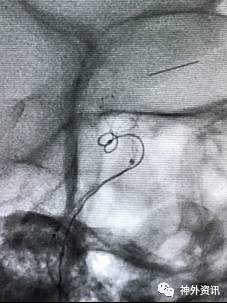

病例二

眼动脉动脉瘤,支架释放前,微导管成袢逆行到位

病例三

A1起始段动脉瘤,微导管成袢逆行到位